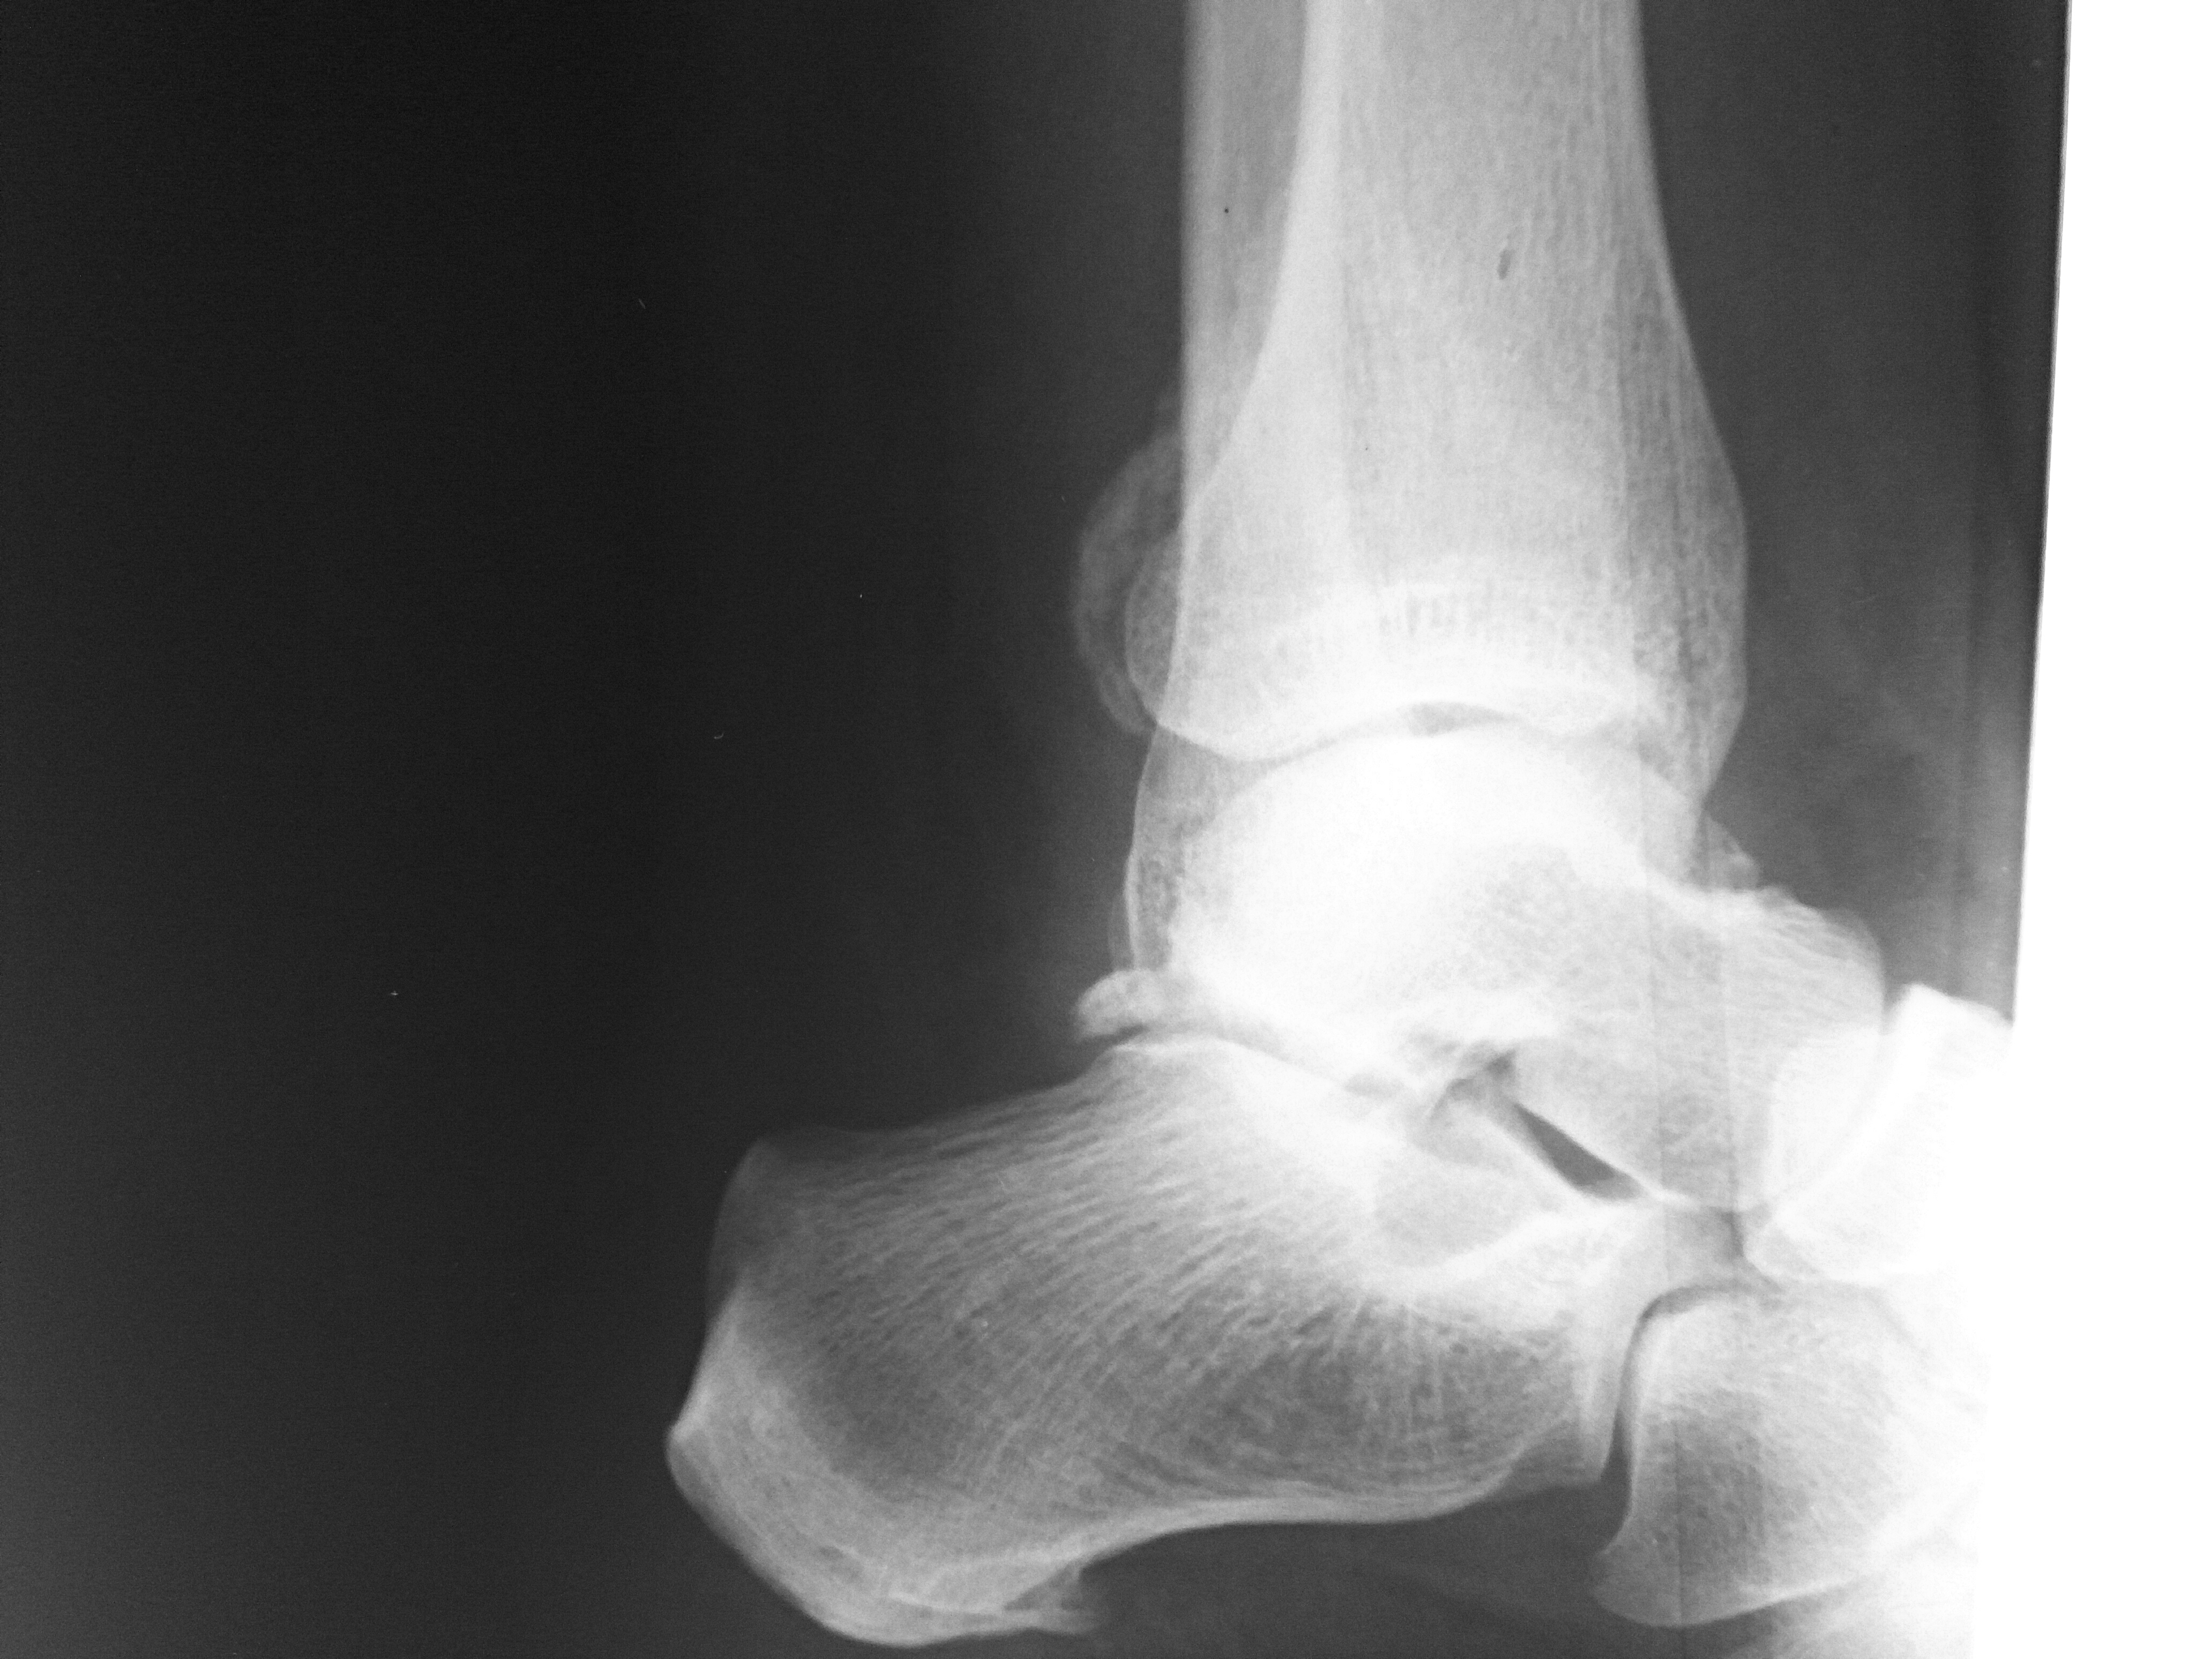

Остеоартроз приводит к деформации сустава различной степени выраженности. В самом начале заболевания этот симптом можно выявить только при рентгенологическом исследовании или при магниторезонансной томографии. Если заболевание будет выявлено на ранних стадиях своего развития, то развитие деформации можно предотвратить или значительно замедлить. Вот почему важно своевременное обращение к врачу!

При диагностике остеоартрита хирург стопы и голеностопного сустава тщательно осматривает стопу на предмет припухлости в суставе, ограничения подвижности и боли при движении.

В некоторых случаях может отмечаться деформация и/или увеличение (шпора) сустава. Для оценки степени заболевания может быть назначен рентген.

Другие тесты могут определить, могут ли другие типы артрита быть причиной болей в лодыжках, такие как анализы крови, которые измеряют воспаление и антитела, чтобы исключить воспалительный артрит, или тестирование суставной жидкости на кристаллы мочевой кислоты при подозрении на подагру.Визуализирующие тесты, такие как рентген, могут помочь подтвердить диагноз и определить степень повреждения сустава.

Как диагностируется артрит стопы и голеностопного сустава?

Диагноз артрита стопы и голеностопного сустава, скорее всего, будет включать следующее:

- Предварительный анамнез, в котором врач задает вопросы о том, когда и где началась боль, а также о факторах, усугубляющих или облегчающих ее.

- Тест, называемый анализом походки, при котором медицинский работник измеряет ваш шаг и то, как вы ходите.

- Рентген.